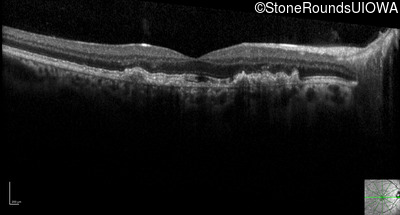

Optical Coherence Tomography - Right - 20/25 -1 sc

Exemplar / OCT Stack